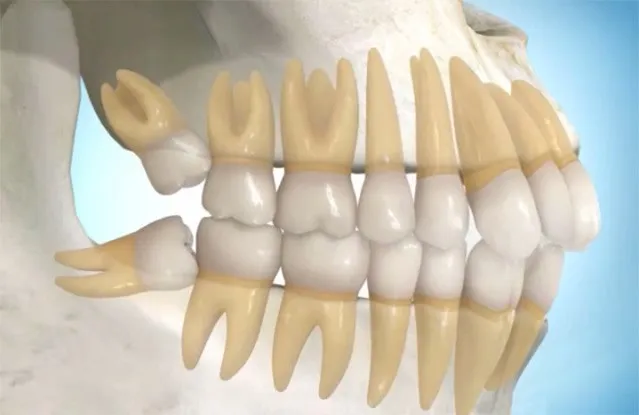

Dental İmplant Cerrahisi: Kayıp Dişlerin Kalıcı ve Güvenilir Çözümü